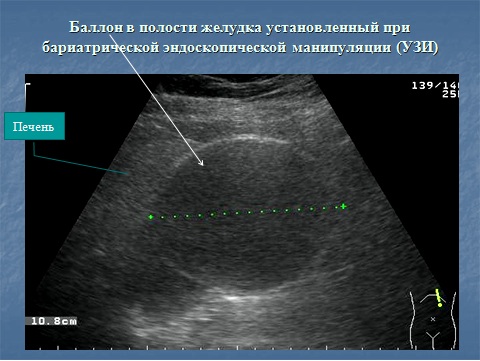

Ультразвуковая диагностика.